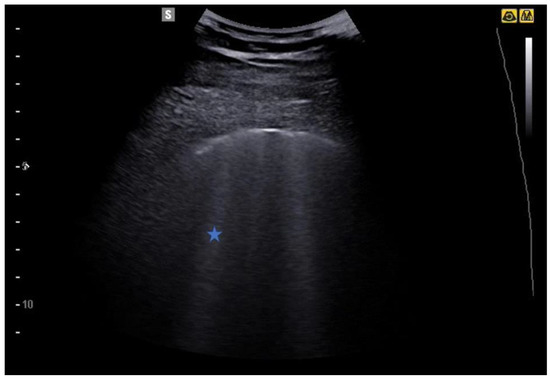

4. Lung Ultrasound on Physiological Lung